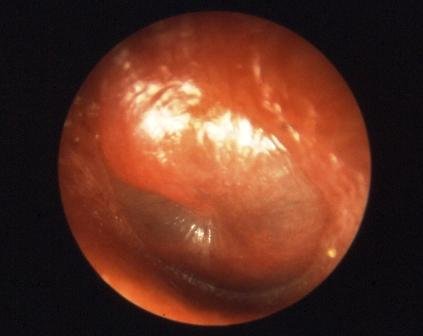

2) Ecocardiograma 0,25 p

A ecocardiografia é considerada o instrumento essencial para o diagnóstico.